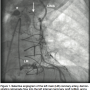

(Figure 1). The right brachiocephalic artery was observed to be heavily calcified, with a 100% ostial occlusion (Figure 2). At this point, a decision was made to intervene on the right brachiocephalic artery occlusion to allow antegrade flow into the right subclavian and carotid arteries to relieve the apparent steal phenomenon from the LIMA-LAD graft.